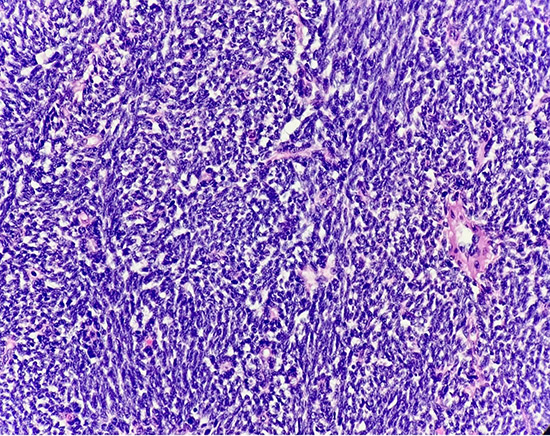

High-grade spindle cell morphology with marked nuclear atypia, hyperchromasia, and prominent nucleoli (High Magnification, 400X).